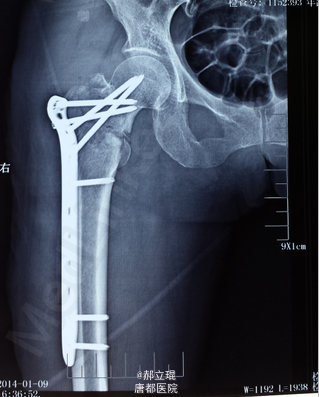

股骨颈基底部

拍X光片,显示股骨颈基底部骨折。

各项指标都正常后,施行股骨颈基底部手术。

术后十天出院,不再疼痛。建议多吃高钙产品。四个月后老人基本能够活动,每天能坚持锻炼。